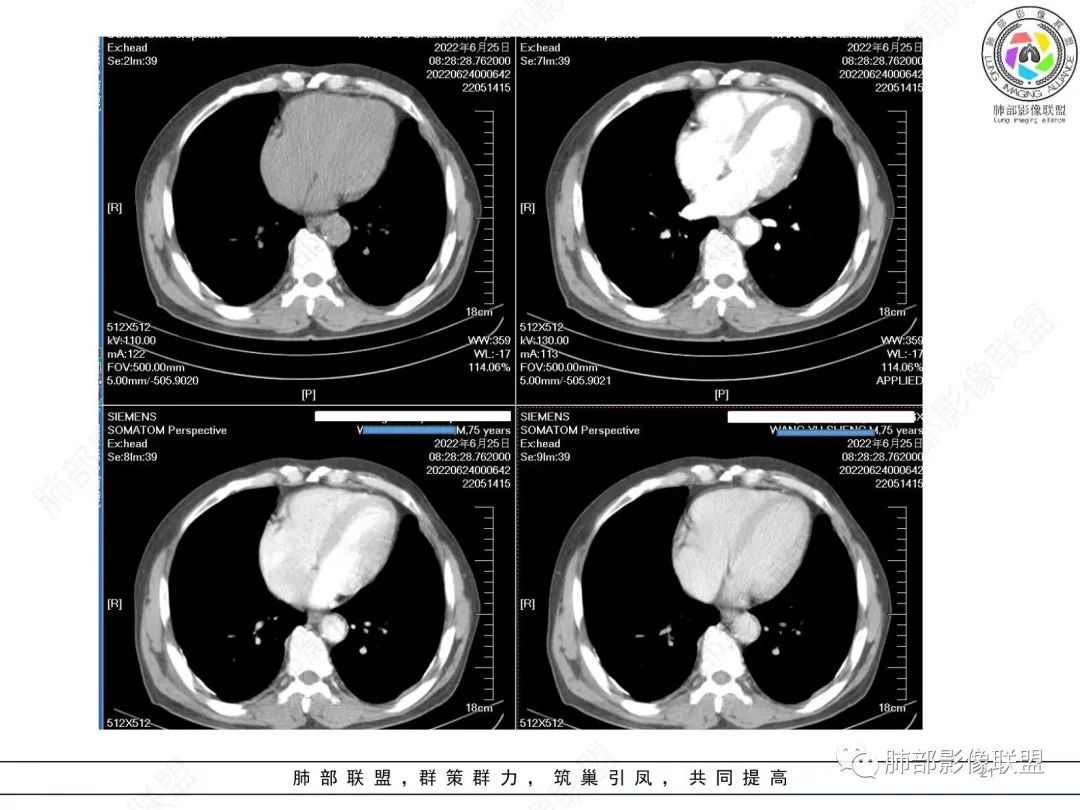

淋巴瘤肯定不符合了。

仅仅只有血管漂浮和支扩支持淋巴瘤。其他细节都是否定淋巴瘤的。

大肿块、表面光滑但深分叶,肺门侧支气管堵塞

我一开始诊断恶性,定在淋巴瘤,还觉得信心满满

回头看,内部支气管近端其实不连续,伴随肺动脉不存在

这两点就不符合

还有如果从支气管的特点考虑黏膜相关性淋巴瘤,其整体应该是边缘不清楚为主,肺炎样为主。